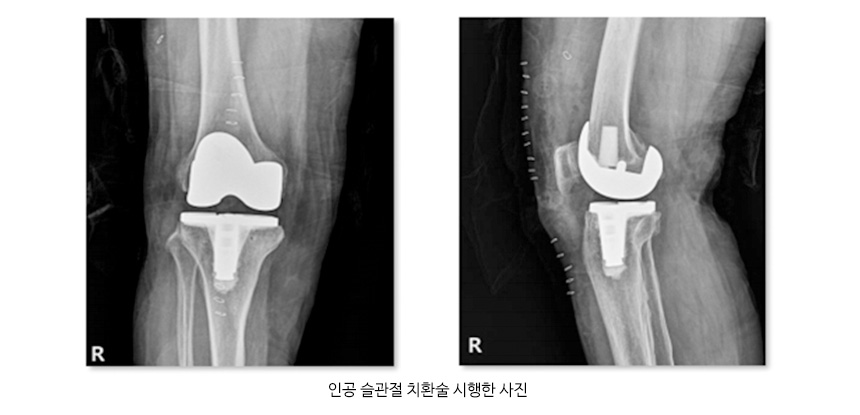

퇴행성 관절염을 치료하기 위해서는 생활습관을 개선하고 약물요법으로 염증을 줄이고 재활치료를 시행하여 증상 완화와 근육위축 방지를 할 수 있으며, 비수술적 치료방법에도 불구하고 증상 호전이 없는 경우 관절경 및 인공관절 치환술을 시행하기도 합니다.

관절염 사진 및 인공슬관절 치환술 사진